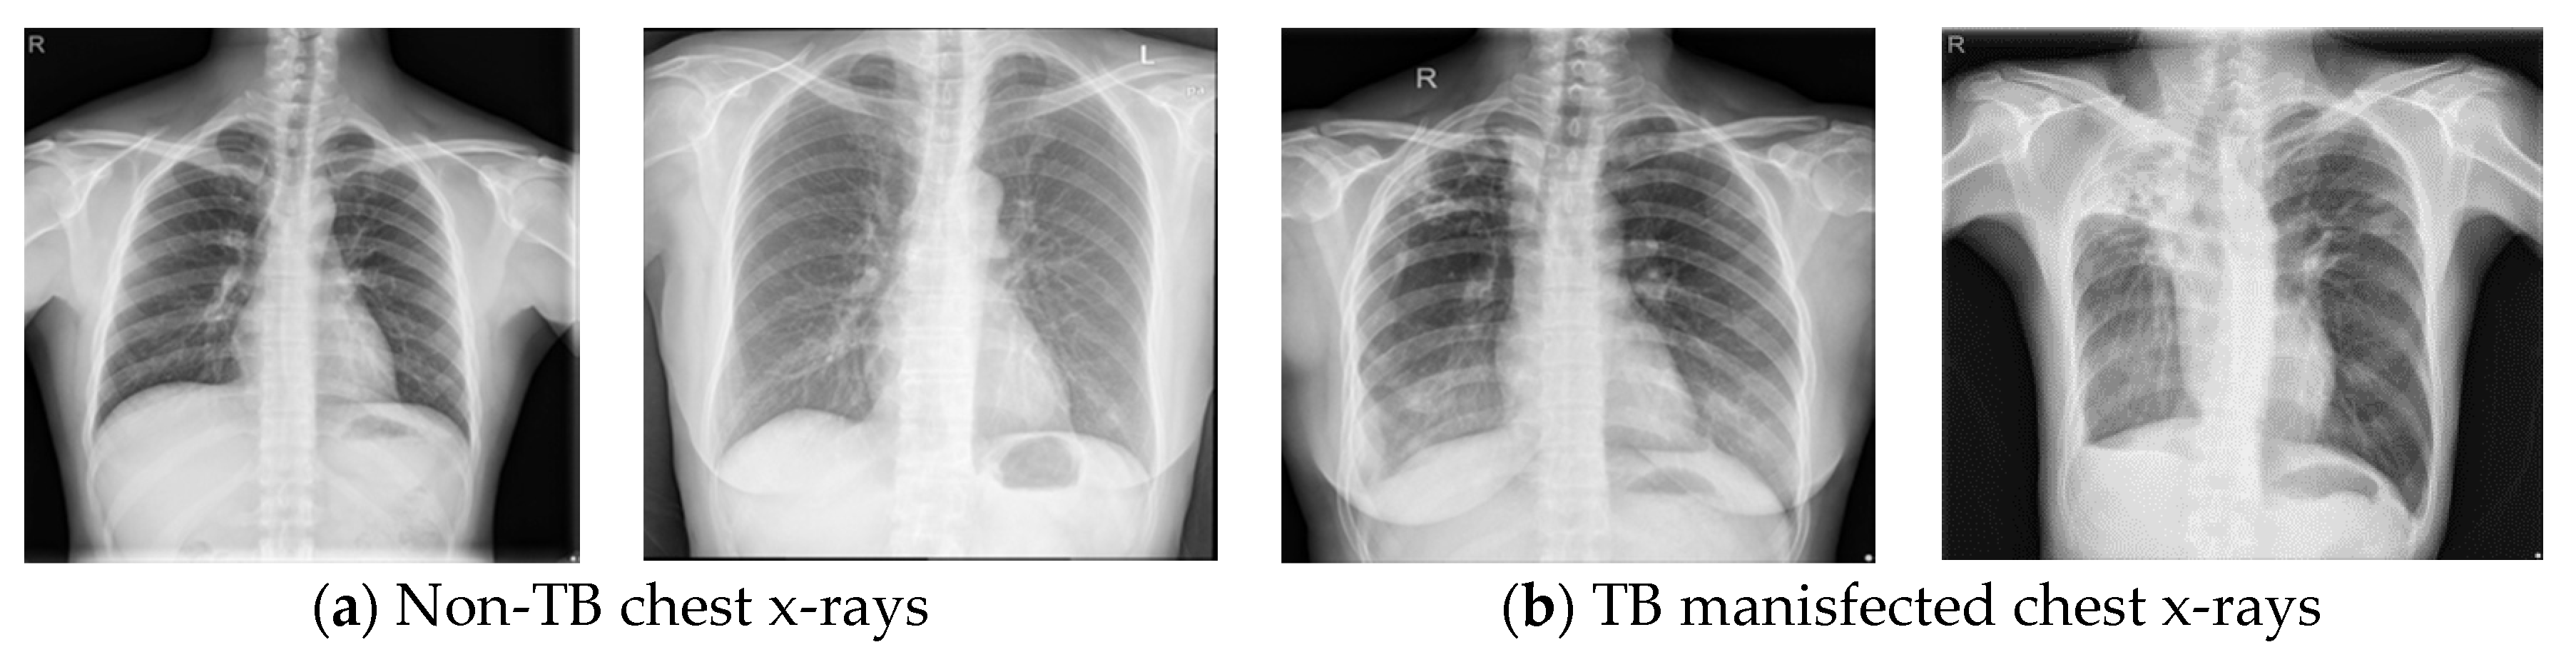

2. Dataset Description